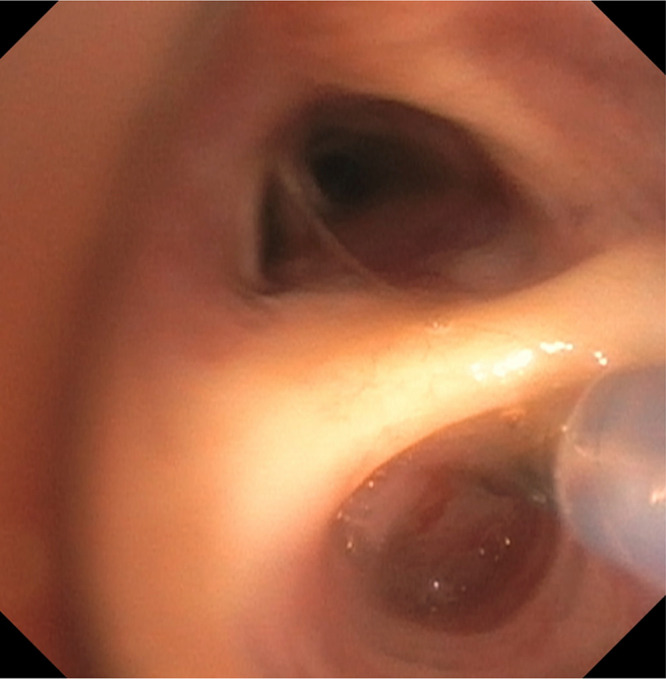

Navigational bronchoscopy is increasingly used to target peripheral pulmonary nodules using electromagnetic navigational platforms (ENB), fluoroscopic navigation, or robotic-assisted bronchoscopy. The selection of equipment largely depends on the availability of technology, expertise, and the characteristics of the nodule and patient. Radial EBUS (r-EBUS) is often combined with these techniques for real-time confirmation of the nodule location. A bronchus sign is considered to have a higher diagnostic yield when biopsy tools can directly reach the nodule. We describe a case series of creating a false airway into the nodule when an eccentric r-EBUS signal is seen to subsequently obtain a concentric signal.

Abstract Image